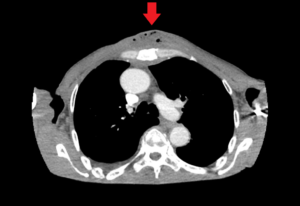

Chest wall abscess, CT axial, annotated. JETem 2024

Chest wall abscess CT axial annotated. JETem 2024